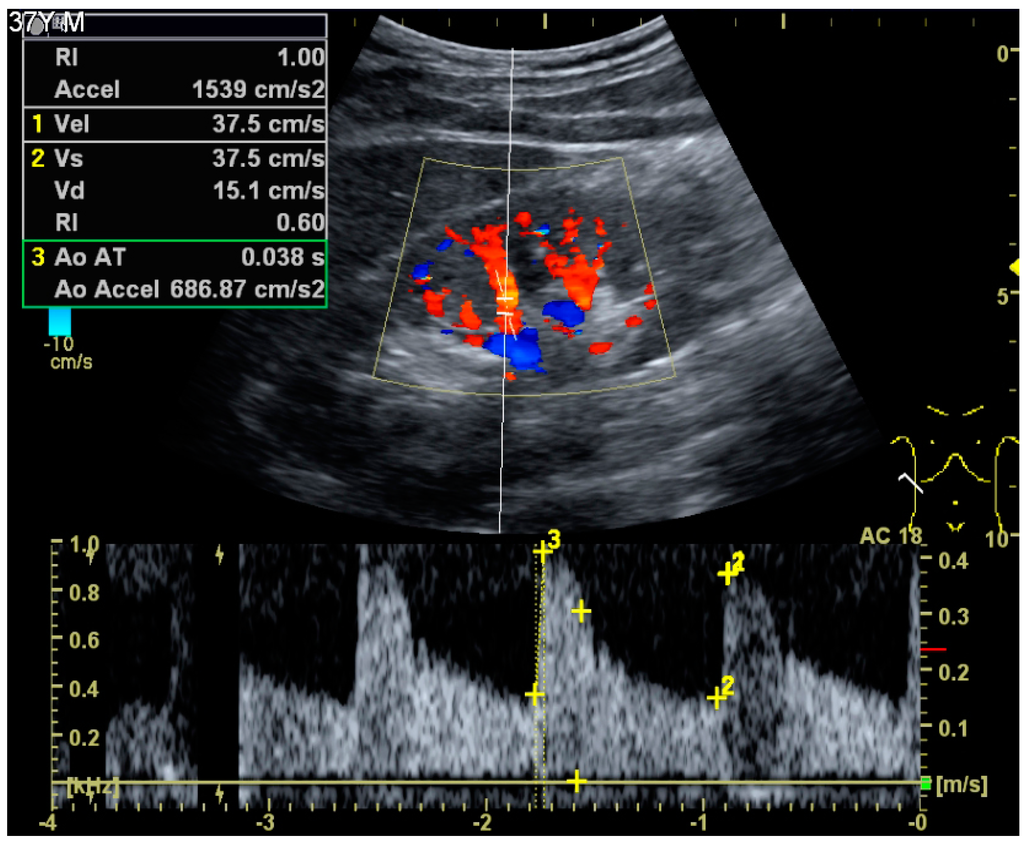

Doppler examination of the kidney is widely used, and the vessels are easily depicted by the color Doppler technique in order to evaluate perfusion. Applying spectral Doppler to the renal artery and selected interlobular arteries, peak systolic velocities, resistive index and acceleration curves can be estimated (Figure 4) [11], e.g., peak systolic velocity of the renal artery above 180 cm/s is a predictor of renal artery stenosis of more than 60%, and the resistive index, which is a calculated from peak systolic and end systolic velocity, above 0.70 is indicative of abnormal renovascular resistance [7].

Figure 4. Doppler ultrasound (US) of a normal adult kidney with the estimation of the systolic velocity (Vs), the diastolic velocity (Vd), acceleration time (AoAT), systolic acceleration (Ao Accel) and resistive index (RI). Red and blue colors in the color box represent flow towards and away from the transducer, respectively. The specrogram below the B-mode image shows flow velocity (m/s) against time (s) obtained within the range gate. The small flash icons on the spectrogram represent initiation of the flow measurement.